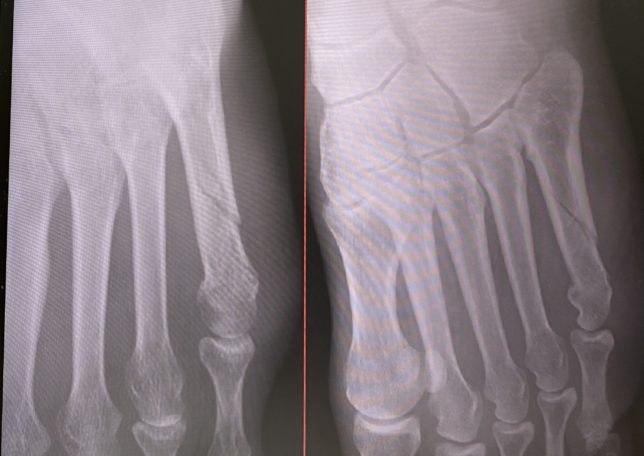

すぐに病院へ行きレントゲンを撮ると、容赦なくボッキリと折れてました。

第五中足骨骨折

12年前と比べると、骨折による治療はあまり変わりはありませんが、ギブスなども簡易的なものになっていました。